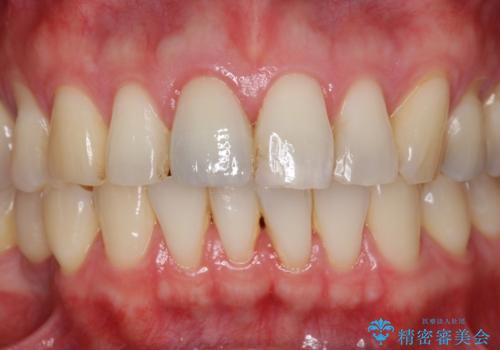

周囲の歯の色調に合わせた、自然なセラミック治療を行うことができましt。

前歯の変色を改善!セラミック治療